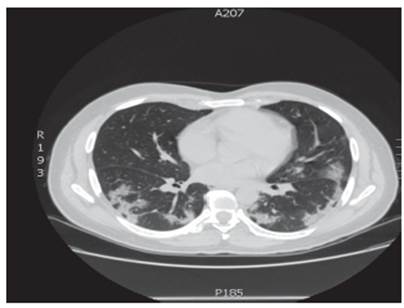

De igual forma, se realizó radiografía de tórax que evidenció infiltrados alveolares periféricos en lóbulo medio derecho y lóbulo inferior derecho e izquierdo y TAC de tórax (Figura 3) que mostró opacificaciones en vidrio esmerilado predominantemente periférico y en lóbulos inferiores con tendencia a la consolidación. Los exámenes de laboratorio realizados durante su estancia hospitalaria se reportan en la Tabla 3.

Fuente: Documento obtenido durante la realización del estudio.

Figura 3 Tomografía axial computarizada de tórax, caso 3.